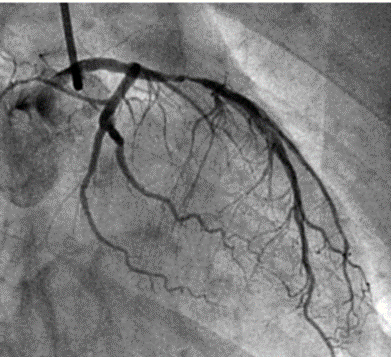

Vad ger upphov till trombosen, erosion eller ruptur?

Bägge

Hur sker aterosklerosutvecklingen?